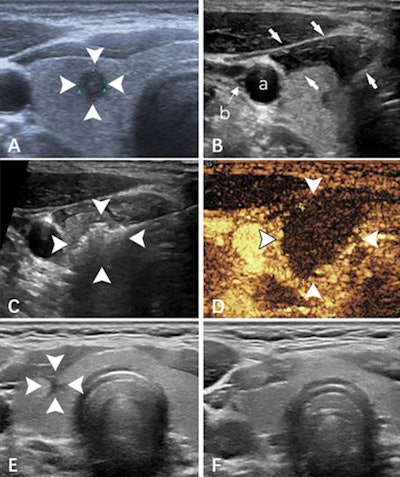

Capsular invasion has been previously identified as an independent risk factor for thyroid lymph node metastasis. Yet papillary thyroid microcarcinomas with ultrasound-detected capsular invasion have been excluded from thermal ablation treatment due to concerns about increasing complications post treatment.

Zheng and co-authors sought to compare the feasibility, effectiveness, and safety of microwave ablation for treating these microcarcinomas with and without ultrasound-detected capsular invasion via a study that included data from 460 patients. Of these, 82 underwent microwave ablation with ultrasound-guided detection of capsular invasion while the remaining 378 did not. The capsular invasion group had follow-up at 20 months while the noninvasion group had follow-up at 21 months.

The team found comparable success rates for microwave ablation with ultrasound for both groups, at 99% for the capsular invasion group and 100% for the non-invasion group. It also reported only one complication (1%) in the capsular invasion group compared with 11 in the noninvasion group (3%). On follow-up, the team reported clear shrinkage of the ablation zone in both groups, at 97% in the capsular invasion group and 96% in the noninvasion group.